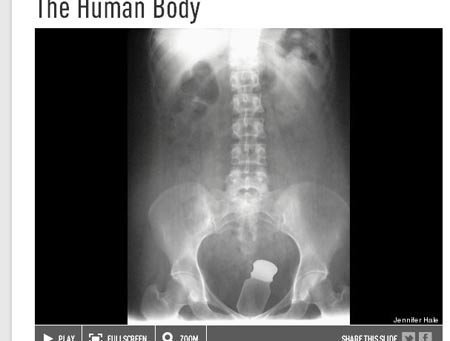

Đôi khi, các bác sĩ ngạc nhiên nhất không phải là khi họ phát hiện ra các vật thể trong cơ thể bệnh nhân, mà là họ không hiểu bằng cách nào mà vật thể này lại chui vào được tận đây. Trên đây là hình một cái chai trong người bệnh